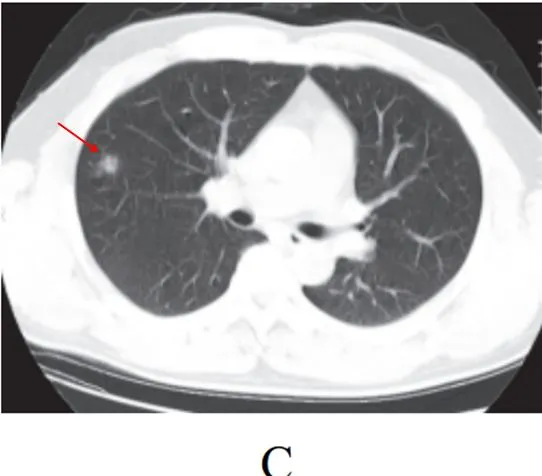

病灶形态以三种类型为主,即多叶多灶分布病灶(图 2-2A) 、单叶片状病灶(图 2-2B)和孤立性类圆形病灶(图 2-2C)

多叶多灶分布病灶(图 2-2A)

单叶片状病灶(图 2-2B)

孤立性类圆形病灶(图 2-2C)